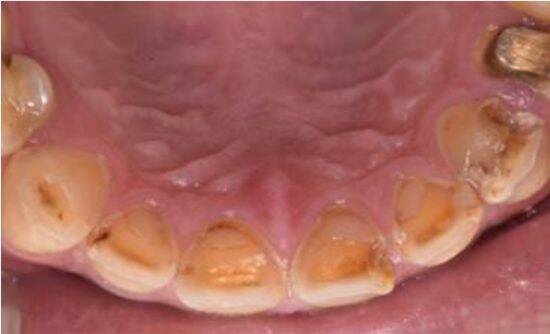

エナジードリンクやスポーツ飲料には糖分が多く、唾液が減った口内ではむし歯・歯周病リスクがさらに高まります。さらに、こうした飲み物は「口が乾きやすくなる」だけでなく、「歯そのものを溶かしやすい環境」をつくることもあります。むし歯菌によるものではなく、飲食物などの酸によって歯の表面が少しずつ溶けていく状態を「酸蝕歯(さんしょくし)」と言います。

酸蝕歯が進むことで歯に見られる変化には次のようなものがあります。

・歯がしみる

・歯の表面がツヤっと薄く見える

・歯の先端が透けたように見える

・以前より歯が丸く、小さく見える